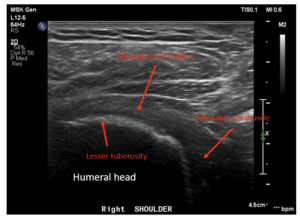

Dynamic ultrasounds performed by a fellowship trained musculoskeletal (MSK) radiologist were obtained 6 months post-surgery and evaluated for integrity of the subscapularis tendon as well as tendon thickness, width, echotexture, and calcification. Additional assessments included a standardized interview and physical examination of subscapularis function (graded belly press test and Gerber’s lift-off test), range of motion, and ASES scores were prospectively collected pre-operatively and post-operatively at 3 months and 6 months.

The subscapularis tendon was intact (healed) in all shoulders as determined by the musculoskeletal radiologist. No tendon tears were observed. Four of 5 patients showed no evidence of tendinosis, while 1 patient showed mild tendinosis. Overall, the echogenic fibrillar architecture of the healed subscapularis tendon appeared normal and aligned. Six-month ultrasounds images for all patients are presented in Figures 5-9. The width of the subscapularis tendon in all patients showed a mean of 0.48 cm maximal tendon thickness and 2.72 cm mean tendon width (Table 2), similar to native tendon (Saltzman et al. 2014). The patients’ ASES shoulder scores showed an average improvement of 33 total points at 3 months and 35 points at 6 months post-operatively (MCID 13.6 +/- 2.3) (O.’Brien, Harley, and Yannas, n.d.). Results of secondary outcome measurements, including subscapularis function and range of motion, are presented in Table 3. All patients exhibited tendon healing without complications or revisions. At the 6-month ultrasound, there was no evidence of the collagen-based implant.

In this five patient case series, the subscapularis tendon in all patients was shown to be intact, with four showing normal fibrillar tendon architecture; one patient showed mild tendinosis and < 25% partial tear. All repairs demonstrate aligned new tissue formation rather than disorganized scar tissue. As evident in Figures 5-9, augmentation of the subscapularis tendon with the collagen-based implant was shown to be safe and effective with excellent healing outcomes at 6 months. Improvements in ASES scores, internal rotation strength and range of motion were also seen with all patients, suggesting the importance of subscapularis tendon healing after anatomic shoulder arthroplasty for optimal outcomes. This pilot study suggests subscapularis tendon augmentation has the potential to improve subscapularis healing rates and function following shoulder arthroplasty. This study is limited by a small sample size, non-randomization, and some heterogeneity in subscapularis management technique. Expansion to a multi-center, multi-surgeon clinical trial would further validate findings.